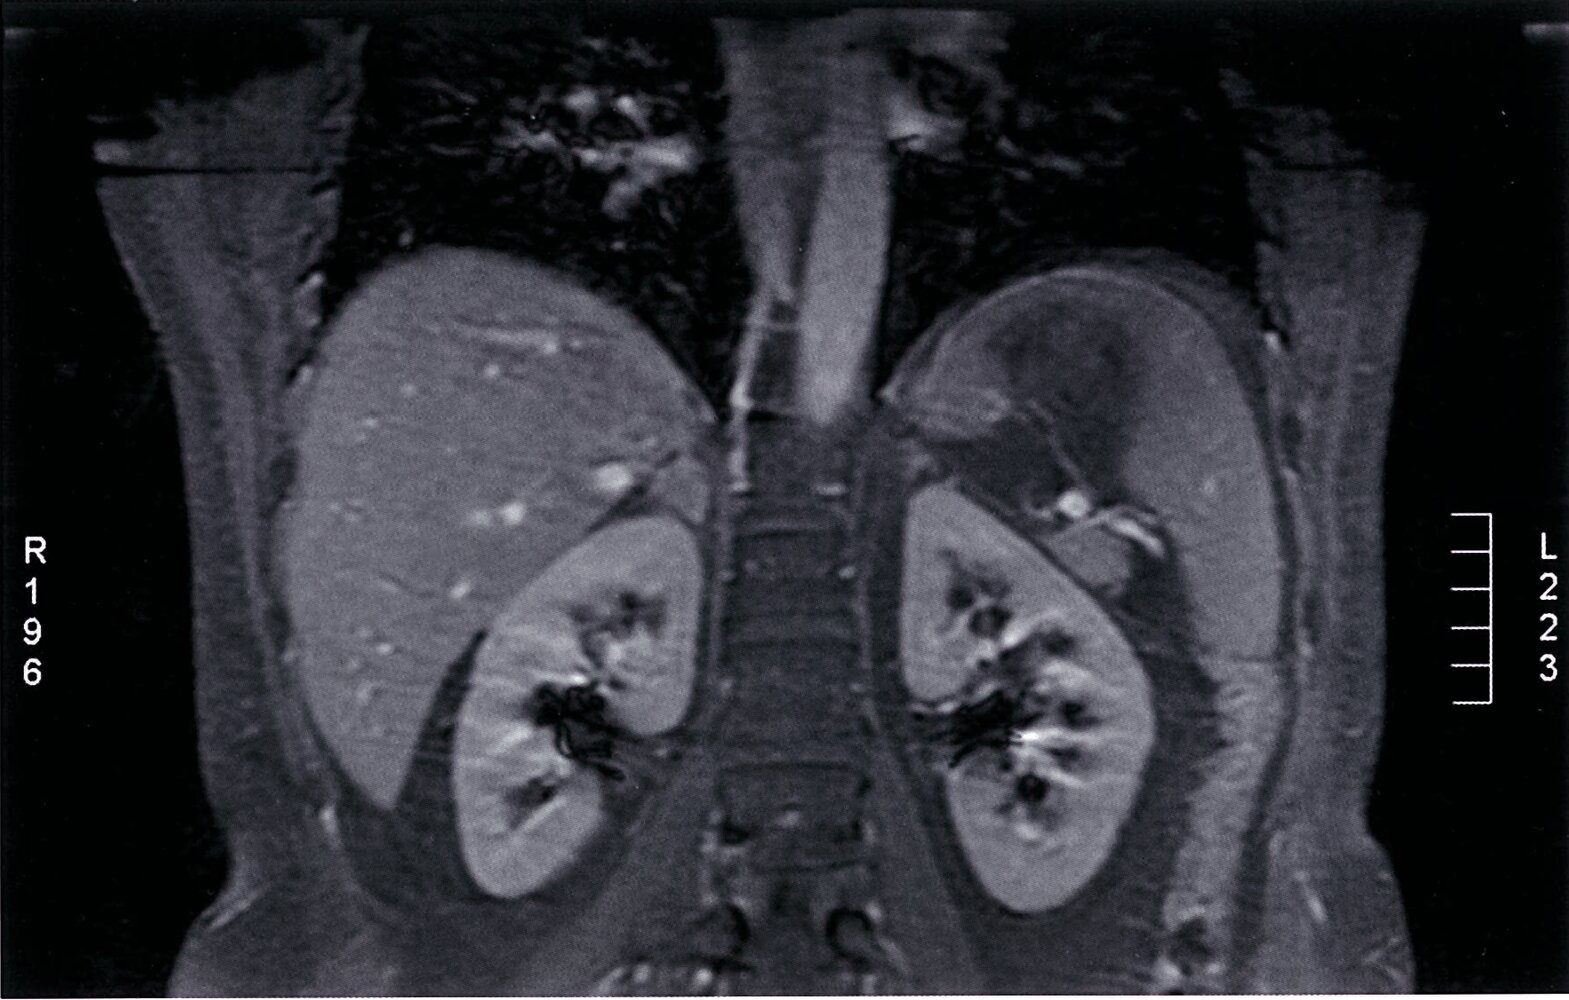

• MRI with chemical shift analysis

• Alternative to CT to identify benign masses and exclude malignancy

• Offers equivalent information to CT